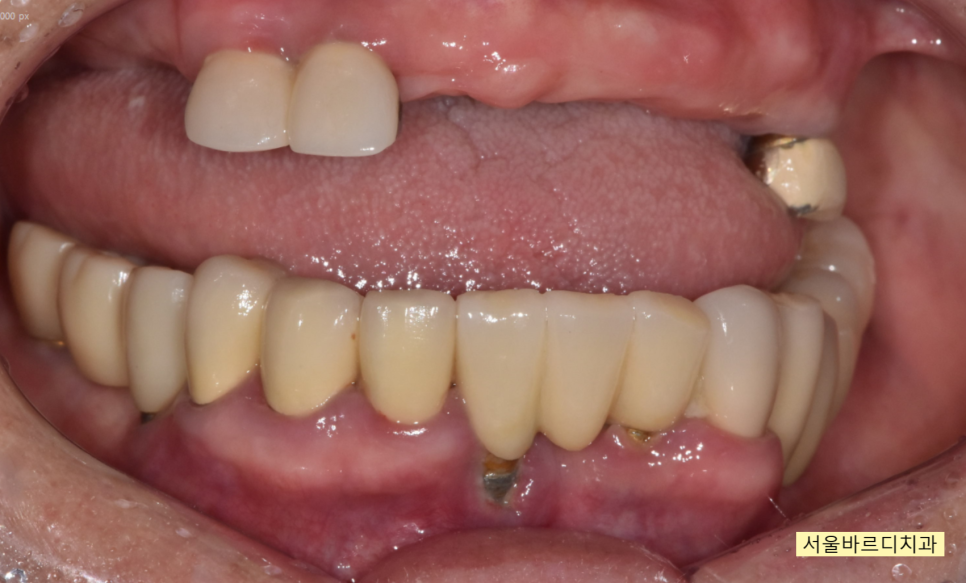

입술을 자꾸 씹어서 불편해요

상일동 치과에 내원해주신

80대 여자 환자분입니다.

현재 윗니 치아의 경우 부분 틀니를 사용중이신데

음식을 먹을 수가 없다 하셨습니다.

자꾸 질겅질겅 입술을 씹다보니

상처가 나서 아프고

편하게 식사도 못하시고 말이죠~~

치료가 끝난 모습입니다.

윗니가 아랫니를 덮는

정상적인 교합으로 마무리 되었습니다.

입술을 씹는 문제는

자연스럽게 해결~~